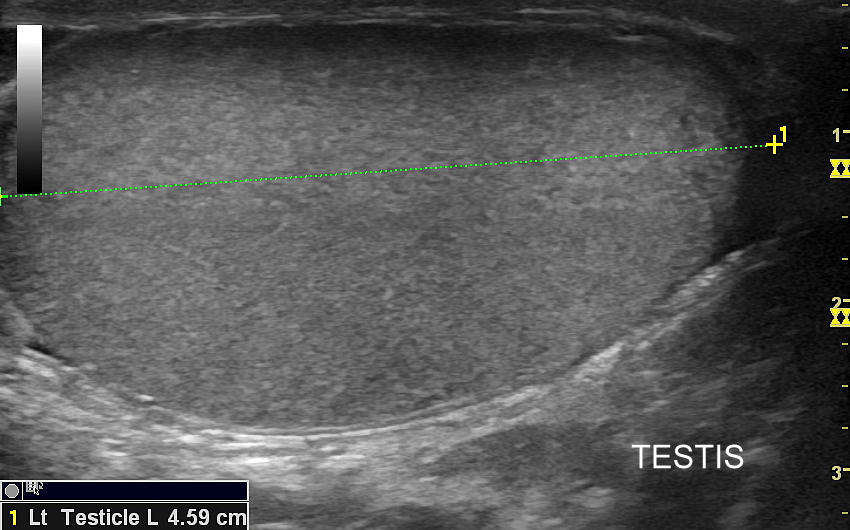

USG moszny i kanału pachwinowego jest podstawową metodą obrazowania jąder, najądrzy, powrózka nasiennego, w tym nasieniowodu oraz towarzyszących im naczyń żylnych i tętniczych. Badanie USG przeprowadzić należy w przypadku wystąpienia bólu i obrzęku jąder, pojawienia się macalnego guzka w obrębie moszny, podejrzenia skrętu lub zapalenia jądra, żylaków powrózka nasiennego, w ramach oceny dojrzewania płciowego chłopców. Kanał pachwinowy bada się także w sytuacji podejrzenia wnętrostwa, przepukliny pachwinowej, w celu oceny węzłów chłonnych, a także nasieniowodu w diagnostyce niepłodności męskiej.

Mosznę bada się aparatem USG wyposażonym w dedykowaną sondę o wysokiej rozdzielczości przeznaczoną do oceny jąder i drobnych struktur moszny, koniecznie z zastosowaniem trybów dopplerowskich, takich jak Doppler kodowany kolorem, Doppler spektralny i obrazowanie mikrounaczynienia. Dopełnieniem badania USG jąder jest użycie w stosownych przypadkach trybu elastografii oraz trybu USG z kontrastem (CEUS). Lekarzem, który pierwszy we Wrocławiu i na Dolnym Śląsku przeprowadził badanie CEUS jąder jest dr Tomasz Szczepański.